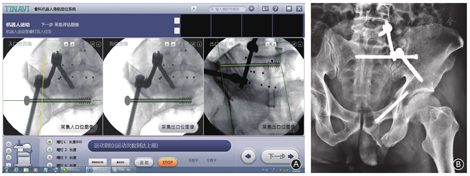

本文以TiRobot骨科手术机器人(北京天智航医疗科技有限公司,中国)为例探讨骨科手术机器人的临床应用及其相关问题。TiRobot是一种基于目标图像进行空间映射和钉道规划的手术辅助定位导向系统,2016年已成功实现产品化装机。该机器人拓宽了微创手术范围,具有操作准确、性能稳定、可重复性好等特点,为骨盆髋臼骨折的微创治疗提供了一种智能化解决方案,在循证医学的框架内使手术方式的个体化选择成为可能[5,6]。目前TiRobot已研发至第三代,并相继推出了天玑®骨科手术机器人1.0和2.0两款应用产品,主要适用于创伤骨科和脊柱外科的微创手术治疗。

采用先进的导航技术,对位于不同坐标系的获取影像进行对准叠加并自动注册,可加快匹配算法,缩短图像生成时间,同时能有效防止术中因结构性影像漂移所带来的定位失准。当系统通过数字影像确定好螺钉位置、长度及直径后,装配在机械臂上的套筒即可确定导针方向,避免了术者手部抖动带来的操作误差。其缺点是被动导航,手术过程最终靠术者完成,系统主要提供和指导内置入物的行进路线。

手术机器人功能设置完成后:(1)在机械臂末端安装标尺并放置于手术区域,采集透视影像并自动注册;(2)在目标影像上通过计算机主控系统规划手术路径并测定螺钉参数;(3)机械臂移动至手术部位并在其末端装配导向工具;(4)在定位套筒的引导下完成螺钉固定,此间须辅以必要的多角度影像验证。

TiRobot的主要临床优势:(1)可规划三维手术方案;(2)机械臂可提供六自由度多向活动,执行端可代替人手掌握内固定物的行进路线;(3)应用"C"型臂X线透视机即可达到手术要求(兼容二维、三维配准),几乎无须借助CT扫描(脊柱骨盆固定除外),因而简化了手术过程;(4)能提供准确的空间定位和路径导航,系统误差≤2 mm,术中几乎无须修正钉道,术后CT证实螺钉误差与术前预期结果基本一致;(5)缩短了手术时间、减少了术中出血及射线暴露;(6)操作简单,便于快速掌握其技术要领。